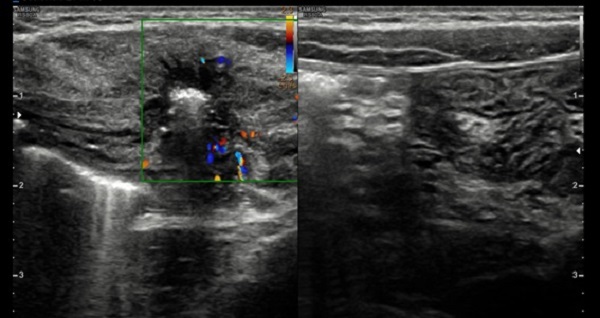

Ante la sospecha de hernia de Spiegel, se pide nueva ecografía orientada, que confirma el diagnóstico (Fig. 1 y Fig. 2).

La ecografía abdominal, prueba complementaria que confirma el diagnóstico, no está exenta de dificultades, debido a que la masa es evanescente. El interior del saco herniario puede estar vacío, pero también puede contener asas intestinales o el testículo ipsilateral, cuando se asocia a criptorquidia. La ecografía Doppler valora si hay estructuras vasculares implicadas.